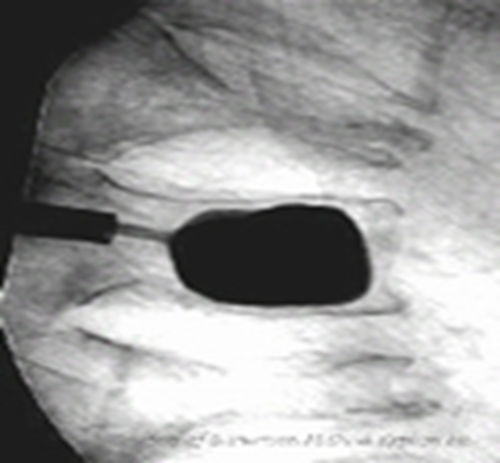

放入可扩张球囊,确保球囊位于椎体内(扩张前透视)扩张球囊:先加入2ml左右造影剂,同时时观察压力表,后每次增加造影剂0.5ml,透视至椎体扩张到满意程度,球囊系统压力控制在15个大气压左右。

注意:扩张球囊时对侧骨钻要抽出

球囊停止加压:A.终板抬高,达到治疗时B.球囊靠近骨皮质或终板时C.对比剂已注入4MLD.扩张压力已达到15个大气压左右